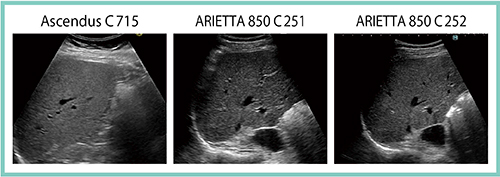

高画質を実現する重要な要素として,ARIETTA 850ではプローブが一新された。腹部用のコンベックスプローブ(C252)では,単結晶の圧電セラミック素子が採用されたことで従来よりも高感度・高フレームレートを実現し,多方向同時受信(多パラレル受信)が可能となった。同社の「HI VISION Ascendus」でのC715プローブの画像と,ARIETTA 850でのC251プローブの画像,およびC252プローブの画像を比較すると,C252プローブの画像が最もきめ細かく描出されているのがわかる(図1)。

図1 従来型プローブ(C715,C251)と新型プローブ(C252)の画像比較